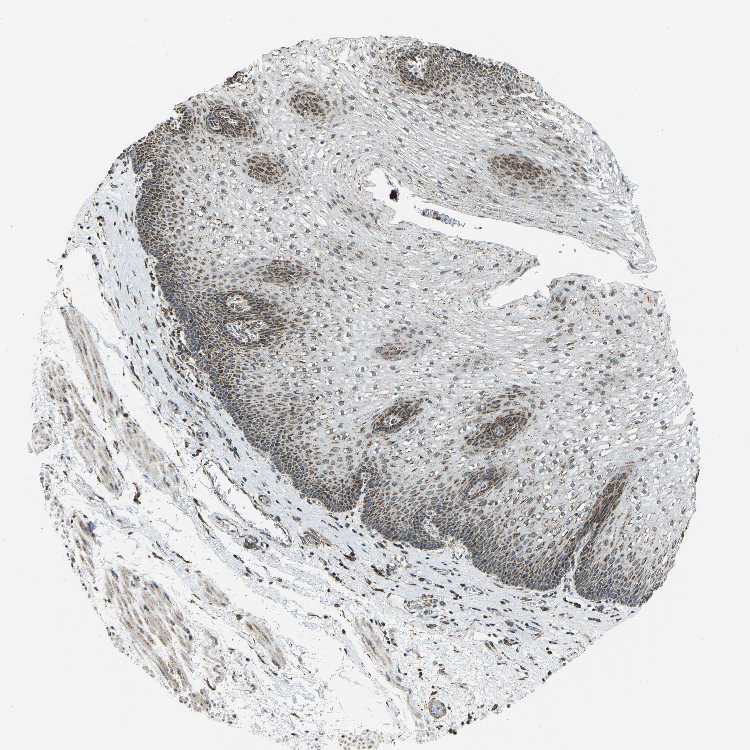

ESOPHAGUS - Antibody stainingi

Antibody staining in the annotated cell types in the current human tissue is reported as not detected, low, medium, or high, based on conventional immunohistochemistry profiling in selected tissues. This score is based on the combination of the staining intensity and fraction of stained cells.

Each image is clickable and will lead to virtual microscopy that enables deeper exploration of all samples and also displays staining intensity scores, fraction scores and subcellular localization as well as patient and tissue information for each sample.

Antibody HPA019232Antibody HPA021497Antibody HPA021768

Squamous epithelial cells HighLowHigh